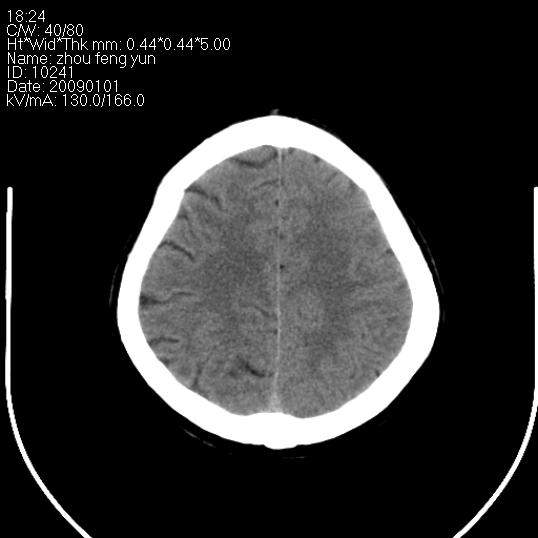

以下是引用hhcckk在2009-1-1 16:39:00的发言:[br]胼胝体嘴、膝部及部分体部发育不全,为囊状影替代,两侧侧脑室分离,脑室后角扩张[br][br]诊断:胼胝体发育不良[br][br]胼胝体发育不良(dysgenesis of the corpus callosum)是最常见的颅脑畸形,是胚胎期背部中线结构发育不良的一种形式。主要包括胼胝体缺如和部分缺如。胼胝体发育不良还可合并其他畸形,如胼胝体脂肪瘤、蛛网膜囊肿、脑膨出、chiari畸形、灰质异位症、脑回畸形等。[br][br]ct诊断要点:[br]1. ct横断扫描可见两侧侧脑室明显分离,脑室后角扩张,形成典型的蝙蝠翼状侧脑室外形。[br]2. 第三脑室扩大并向上插入两侧脑室体部之间,严重者第三脑室可上移到两侧大脑半球纵裂的顶部。在ct冠状扫描位显示更清。[br]4. 胼胝体畸形常伴有脂肪瘤,可测到其特征性脂肪密度。部分脂肪瘤的边缘可出现线样钙化[br]